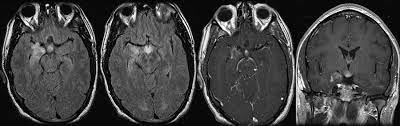

Primary Whipple Disease Of The Brain Case Report With Long Term Clini Ndt

Mr Imaging Of Central Nervous System Whipple Disease A 15 Year Review American Journal Of Neuroradiology

Cerebral Whipple S Disease Laboratory Data And Mri Findings Download Table

Diagnosis And Management Of Whipple S Disease Of The Brain Practical Neurology